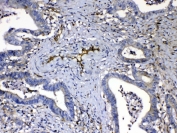

IHC testing of FFPE human breast cancer tissue with HOMER3 antibody at 1ug/ml. Required HIER: steam section in pH6 citrate buffer for 20 min and allow to cool prior to testing.